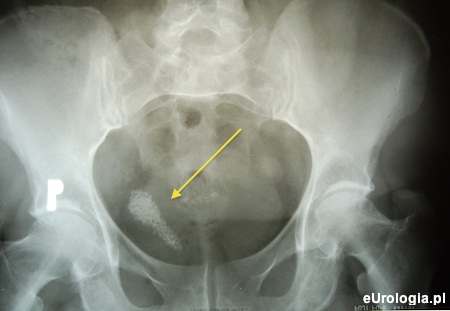

Zdjęcie przeglądowe jamy brzusznej uwidoczniło maczugowaty cień wapienny o wymiarach 60 × 12 mm w miednicy małej po prawej stronie (ryc. 1). Od tomografii komputerowej jamy brzusznej odstąpiono ze względu na awarię aparatu.

Rycina 1. Zdjęcie przeglądowe jamy brzusznej - w miednicy mniejszej patologiczne cienie licznych złogów w rzucie kikuta moczowodu

Cienie wapienne w miednicy małej w rzucie moczowodu u pacjentów po nefrektomii z nawrotowymi infekcjami układu moczowego lub ropomoczem, mogą sugerować patologię w obrębie kikuta moczowodu.